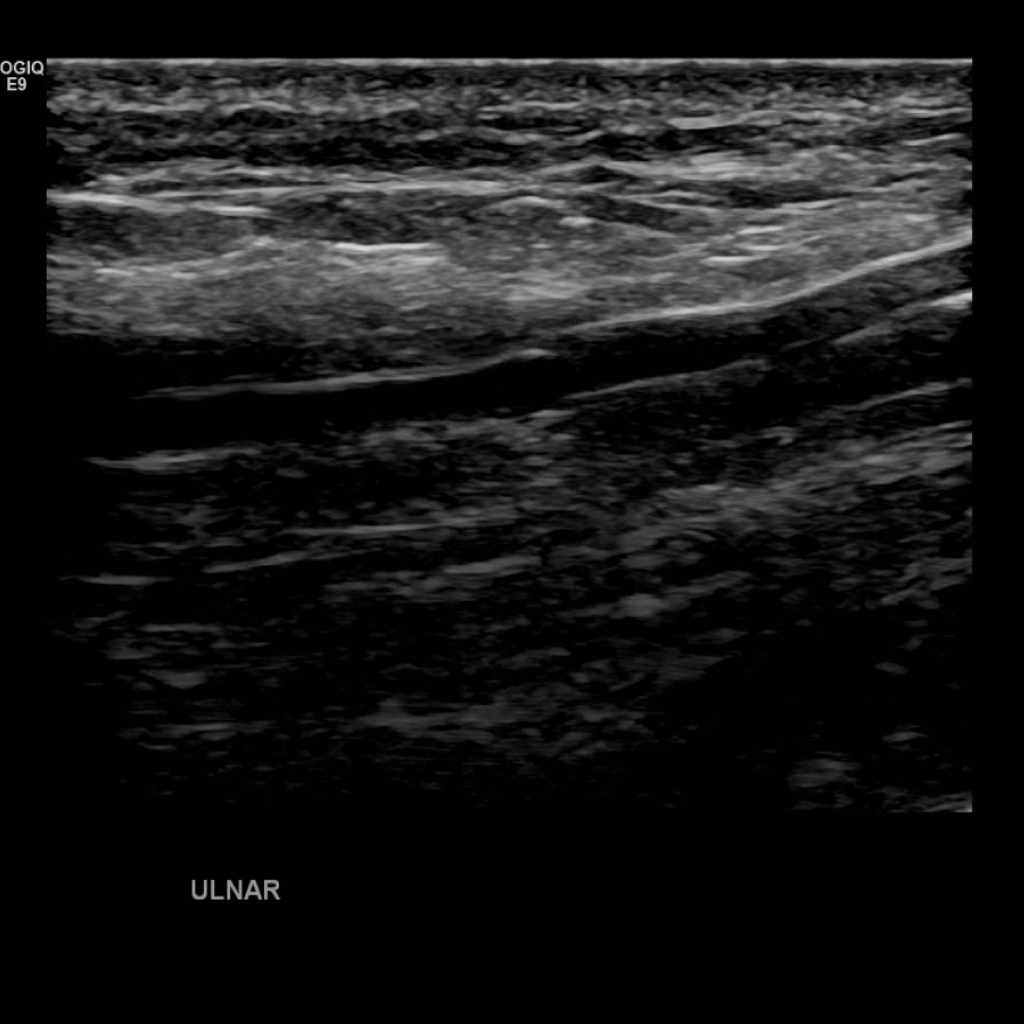

Scan the ulnar veins in grey scale, compression, color doppler and spectral doppler